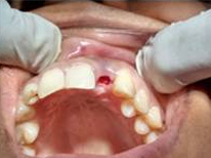

Single Tooth Implant

Drilled socket for Implant